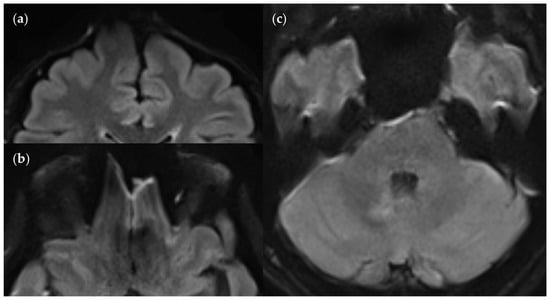

3.3.3. Positional Dependence of SNR and CNR in FLAIRUF

4.3. Limitations of the FLAIRUF Images

4.5. Outcomes Correlated with Technical Features